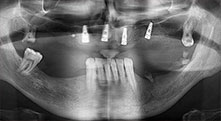

Bratu: We routinely use the instruments for harvesting bone blocks and splitting alveolar ridges. We also use the Piezomed B6/B7 for osteotomy of impacted teeth and removing failed implants. All indications that require deep, clean cuts.

Bratu: We prefer to harvest bone from the external oblique ridge of the posterior mandible, not from the interforaminal region. After the soft-tissue incision, we use the new saws to define the amount of bone to harvest. With this approach, we also use them for the entire preparation in almost 80% of cases. We may also use other piezo instruments and then at the end a chisel to mobilize the block. We find that this is a very effective surgical technique.

Bratu: We like to use the sandwich technique for augmentation in the lateral mandible. A bone cover is prepared with the piezo saw and the crestal fragment is fixed with microscrews. We place a mixture of autologous bone and xenogenic bone replacement material in between. This works very reliably. You should always ensure sufficiently dimensioned vertical cuts when splitting the alveolar ridge in the mandible. Otherwise the bone may fracture easily.